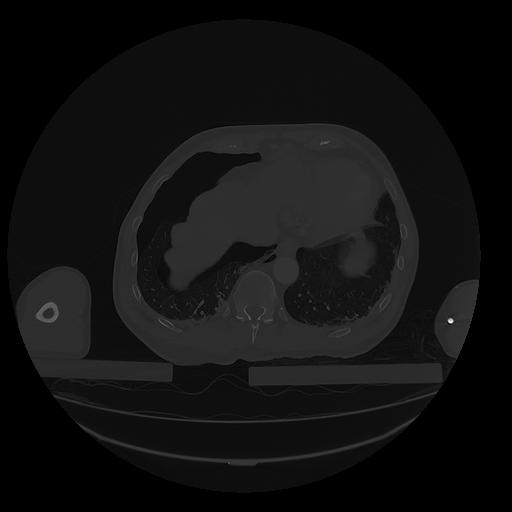

31 PULMON,CE,Vol,1.0,PULMON,,